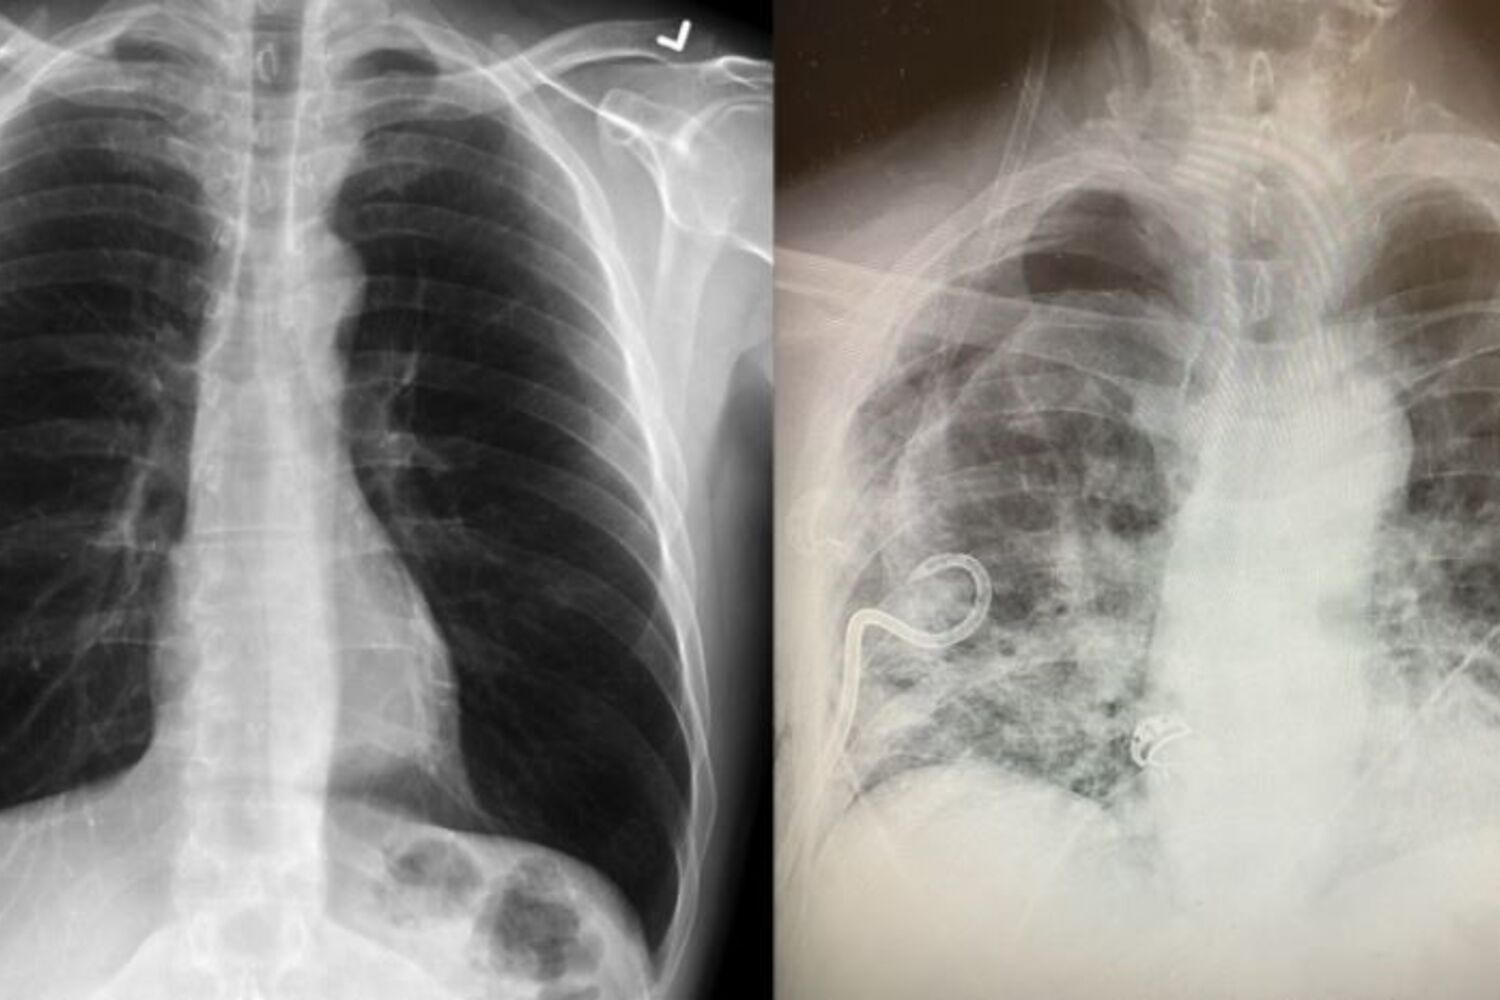

Uma doente, cujos pulmões foram gravemente danificados pela Covid-19, recebeu um transplante de pulmão de doadores vivos.Um estudo revelado no início deste ano mostrou que mais de 1700 pacientes da cidade chinesa de Wuhan, considerada o epicentro da pandemia, apresentaram raio-X onde era possível observar danos graves nos pulmões meses após a infeção.

Um estudo revelado no início deste ano mostrou que mais de 1700 pacientes da cidade chinesa de Wuhan, considerada o epicentro da pandemia, apresentaram raio-X onde era possível observar danos graves nos pulmões meses após a infeção.